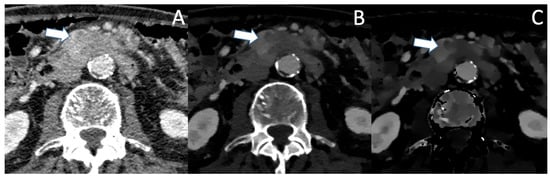

In pretreated PDAC following neoadjuvant chemotherapy, efficacy of conventional CT in staging and evaluation of resectability is severely impaired, with studies showing underestimation of therapy response by overestimation of tumor size and vascular conflicts, possibly leading to falsely excluding patients from curative treatment [50]. More accurate delineation of tumor margins in a pretreated patient with PDAC in VMI and ID is shown in Figure 2. Spectral CT might especially be beneficial for those patients, though data on that matter are currently sparse and further studies are needed. Additionally, MRI with diffusion weighted imaging could provide a better differentiation between tumor tissue and fibrosis, but data on that matter currently only exist for other malignancies, such as rectal cancer [51].

Figure 2. A patient with PDAC after neoadjuvant chemotherapy in conventional CT (A), VMI (B) and ID (C) in the portal venous phase. The small residual tumor (arrow) is barely visible in the conventional image and no statement about vascular association can be made. VMI and ID show a well-demarcated tumor which shows contact with the VMS, with no clear evidence of vascular infiltration.